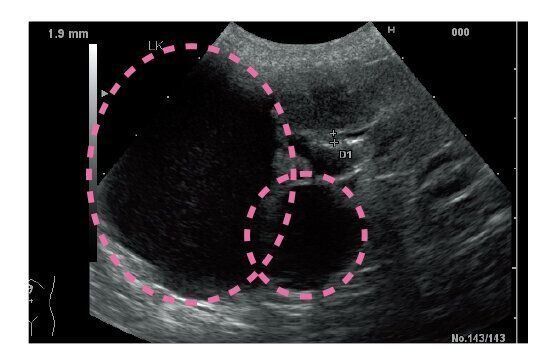

多発性嚢胞腎[たはつせいのうほうじん]

《腎臓内にできものがあらわれ、腹部を圧迫する》

なんらかの原因で、腎臓の中に嚢胞(のうほう)という袋状のものが多数できる病気です。この嚢胞には液体が入っているため、たくさんできると腎臓に負担がかかり、機能が低下して、慢性腎障害の症状が見られることも。初期は無症状のことが多く、症状がなくとも腎臓をエコー検査で診てもらおうと思う飼い主さんも少ないため、見逃しがちに。

腎臓内の嚢胞